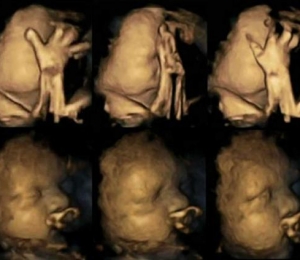

Doctorul Nadja Reissland a studiat radiografiile 4D a 20 de mame care aşteptau un copil, 4 dintre ele fiind fumătoare, înregistrând mii de mişcări minuscule ale fătului în săptămâna 24, 28, 32 şi 26 de sarcină.

În urma acestui studiu, s-a descoperit că bebeluşii nenăscuţi al celor patru mame fumătoare se ating pe faţă în mod frecvent, mai des ca ceilalţi. În mod normal, bebeluşii se mişcă în burtă pe măsură ce cresc şi deprind controlul membrelor.

Rezultate doctorului Reissland indică că mamele care fumează pot îngreuna dezvoltarea sistemului nervos al fătului.